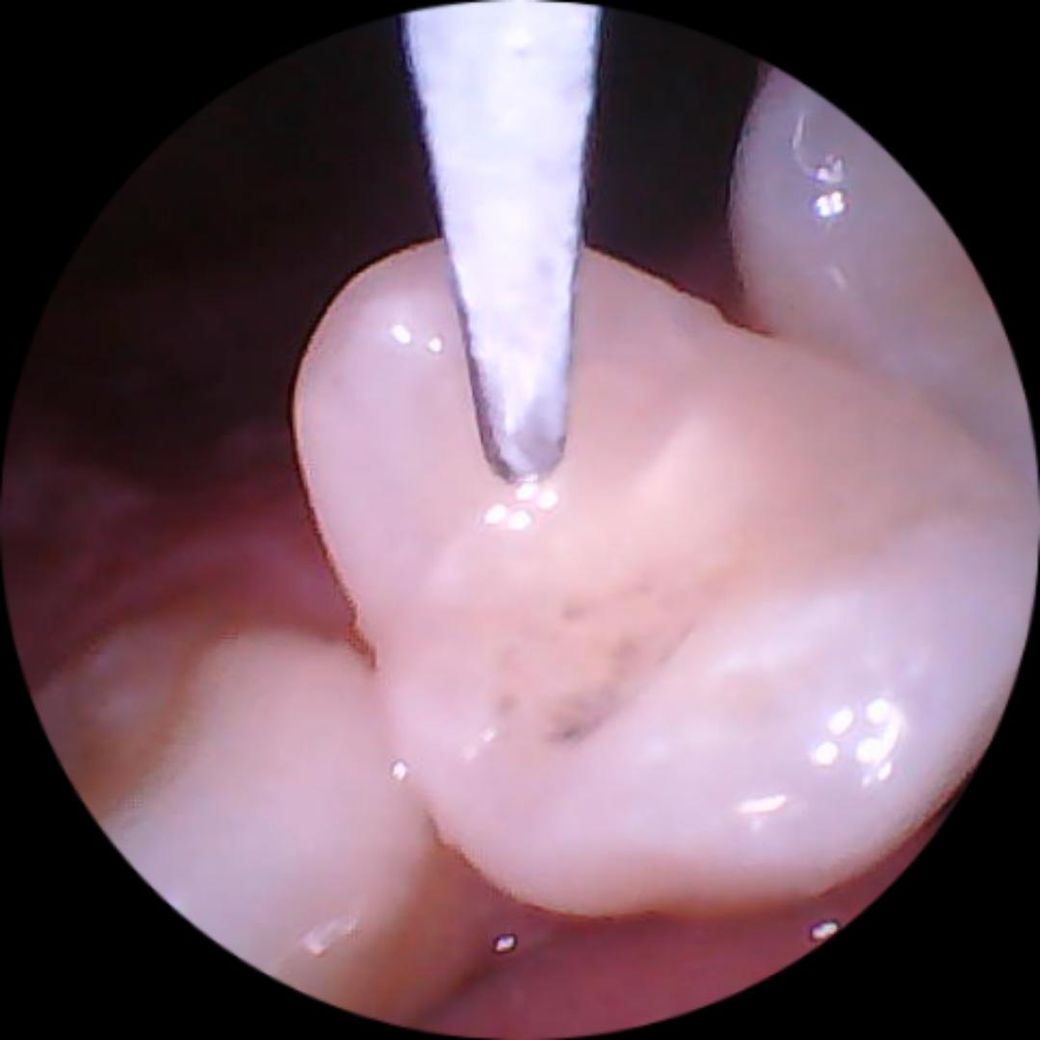

• 2번 째 사진

현재 레진부분이 착색되어 있는 것으로 보이며, 만약 통증이 동반시에는 충치가 더 진행되었을 가능성이 있습니다. 치석제거기로 임의로 제거시 건강한 치아까지 갈리고 범랑질이 손상될수 있기에 반드시 안전하게 치과에서 조치를 취하길 권합니다.

레진치료를 한곳에 착색이 발생한거 같은데 치과에 가셔서 착색제거를 받아보시는게 좋을것같습니다. .

레진외부에 스케일러와 비슷한 진동의 도구가 닿게 되면 손상이 되면서 검은색이 생길수 있습니다.